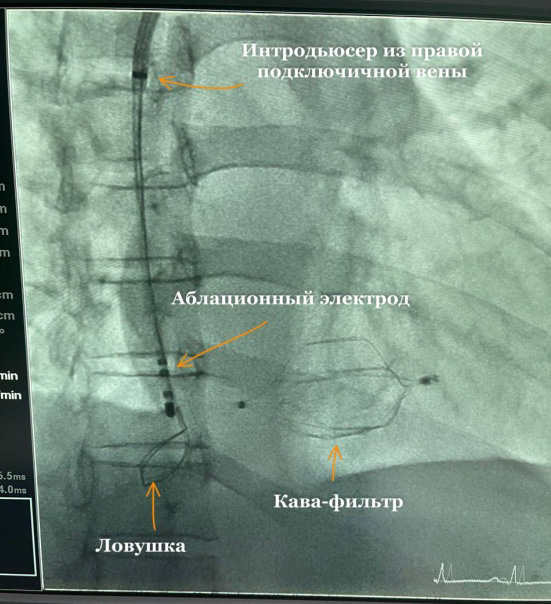

Техника выполнения операции. Выполнена пункция левой подключичной вены, установлен интродьюсер, доведен до уровня правого предсердия. Далее по интродьюсеру был проведен аблационный электрод, чтобы зацепить КФ и подтянуть назад в правое предсердие, однако множественные попытки не дали особого результата, так как фильтр был фиксирован в правом желудочке. Было решено провести десятиполюсный управляемый катетер в правый желудочек и ловушку, после чего была выполнена фиксация КФ (рис. 3) и ее тракция, при этой манипуляции отмечались противодействие тракции и желудочковые аритмии, которые купировались медикаментозно. В результате аккуратными круговыми движениями удалось выполнить смещение КФ в полость правого предсердия, в данной позиции КФ был зафиксирован. Далее выполнена пункция правой подключичной вены, по ней был проведен интродьюсер до правого предсердия для правого коронарного катетера и ловушки. Ловушкой был зафиксирован кончик кава-фильтра и аккуратно удален через правую подключичную вену вместе с интродьюсером (рис. 4).

Рис. 3. Ангиография. Кава-фильтр в полости правого предсердия и желудочка